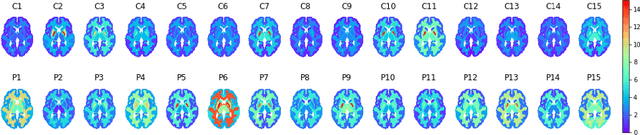

Although neural networks have proven very successful in a number of medical image analysis applications, their use remains difficult when targeting subtle tasks such as the identification of barely visible brain lesions, especially given the lack of annotated datasets. Good candidate approaches are patch-based unsupervised pipelines which have both the advantage to increase the number of input data and to capture local and fine anomaly patterns distributed in the image, while potential inconveniences are the loss of global structural information. We illustrate this trade-off on Parkinson's disease (PD) anomaly detection comparing the performance of two anomaly detection models based on a spatial auto-encoder (AE) and an adaptation of a patch-fed siamese auto-encoder (SAE). On average, the SAE model performs better, showing that patches may indeed be advantageous.